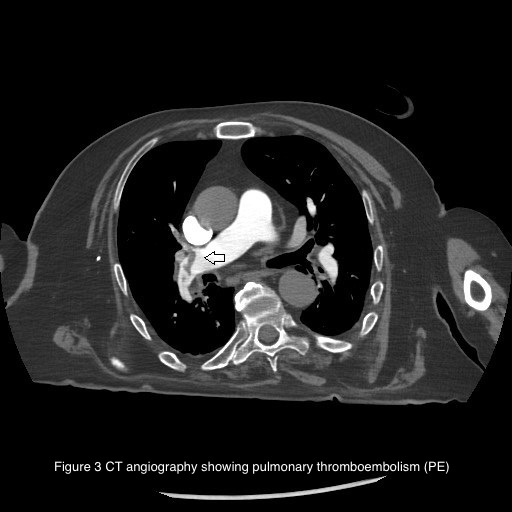

Introduction Ischemic stroke (IS) is caused by the obstruction of cerebral blood vessels, resulting in reduced blood flow and impaired oxygen delivery. It can be caused by atherothrombotic occlusion of large arteries, cerebral embolism or non-thrombotic occlusion of small, deep cerebral arteries. Cardioembolic IS can occur in the presence of various cardiac conditions, such as cardiac masses, patent foramen ovale (PFO), endoluminal thrombosis and sometimes as complication of infective endocarditis (IE). We present the case of a patient admitted to Intensive Care Unit (ICU) after non-cardiac surgery (NCS) who developed IS with high suspicioun of cardioembolic origin. Case presentation A 67-year-old man admitted to ICU developed right-sided hemiparesis after laparoscopic enterolysis surgery. His past medical history included a previous intestinal resection for ischemia. Computed tomography (CT) confirmed IS (1) , suspicious for embolic origin. Atherosclerosis of large cerebral vessels was excluded. Due to post-operative fever, blood cultures were collected and an infection caused by S. Aureus and M. Morganii was detected. Transoesophageal echocardiogram (TEE) was performed to confirm the suspicion of IE with embolization. TEE showed PFO with a significant right–to-left shunt (2B) . Moreover, a floating thrombus was detected in the pulmonary artery (2A) . No IE was found. CT angiography confirmed pulmonary thromboembolism (PE) (3) . Unfortunately, the patient died because of post-operative complications. Discussion The peculiarity of this case is represented by the unexpected aetiology of IS considering the clinical confounding presentation. At first, the most probable expected cause was represented by IE but PE and paradoxical embolization due to large PFO turned out to be responsible of IS. Some studies demonstrate PFO association with increased risk of IS in patients undergoing NCS in different settings. The prevalense of PFO in the general population is estimated at approximately 20-25% but the lack of a systematic screening in patients without IS likely underestimates its prevalence. Currently, PFO closure in addition to anti-aggregation therapy is indicated in patients with IS when a strong causal relationship between PFO and stroke is demonstrated. Further prospective trials are needed to identify a specific population at risk of perioperative IS associated with PFO in order to define systematic screening, prevention plans and improve perioperative outcomes.